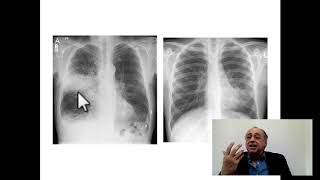

77- Lung Masses

Thoracic # Radiology # Cases # FCPS # FRCR.